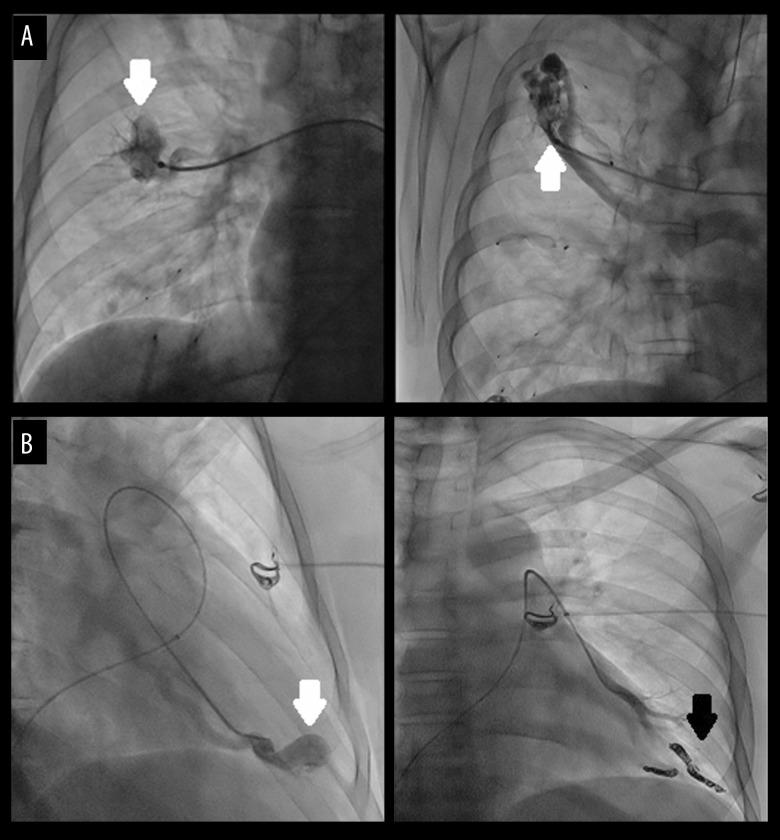

BACKGROUND Hereditary hemorrhagic telangiectasia (HHT) is a rare autosomal dominant genetic disease associated with arteriovenous malformations involving diverse organs. Neurological complications from brain abscesses (BA) secondary to pulmonary arteriovenous malformations (PAVMs) is a serious and recognized, albeit infrequent, medical problem. We report the case of a 37-year-old man with familial HHT and PAVMs who presented with seizures as a manifestation of BA. CASE REPORT A 37-year-old man was admitted for first tonic-clonic seizures. He had a history of recurrent epistaxis and recurrent gastrointestinal bleeds treated with fulguration and oral iron therapy. A diagnosis of HHT was made because the patient met 3 of 4 Curaçao criteria. Physical examination revealed hypoxemia without dyspnea. A chest X-ray detected nodular pulmonary lesions in both lower lobes. Cranial computed tomography (CT) revealed 3 space-occupying lesions. Antiepileptics and dexamethasone were started. Cranial magnetic resonance and positron emission tomography suggested that lesions were BA. Thoracoabdominal CT with contrast revealed several bilateral PAVMs. Blood cultures were repeatedly negative. With the presumptive diagnosis of septic-embolic BA, empirical antibiotic therapy was started for 8 weeks. Neurological symptoms resolved and malformations >2 cm were selectively embolized. A genetic study revealed exon5 mutations in the ENG gene. CONCLUSIONS This report highlights the association between PAVMs in a patient with HHT and development of BA. Clinicians should be aware of this association so that diagnosis and treatment can be provided as fast as possible to ensure the best outcome for the patient. Embolization was performed as preventive treatment, and a genetic study was conducted as it is potentially useful for primary prevention in the patient's offspring.

病例报告 一名 37 岁男性因首次强直阵挛性发作入院。他有反复鼻出血和复发性胃肠道出血的病史,曾接受过电灼和口服铁剂治疗。由于患者符合 Curaçao 标准的 4 项中的 3 项,因此诊断为 HHT。体格检查发现低氧血症而无呼吸困难。胸部 X 线片显示两肺下叶结节性肺病变。头颅 CT 显示 3 个占位性病变。开始使用抗癫痫药和地塞米松。头颅磁共振和正电子发射断层扫描提示病变为 BA。胸腹 CT 增强显示多个双侧 PAVMs。血培养多次阴性。鉴于疑似感染性栓塞性 BA,开始经验性抗生素治疗 8 周。神经系统症状缓解,>2cm 的畸形采用选择性栓塞治疗。基因研究显示 ENG 基因外显子 5 突变。